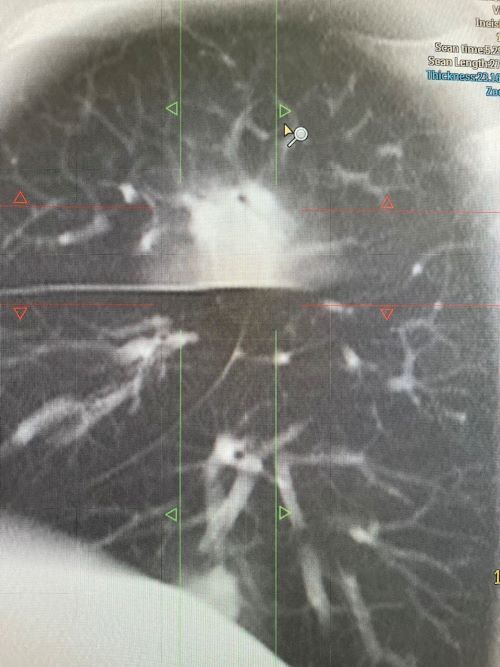

После проведённого сканирования были выявлены поражения в обоих лёгких, с выраженным инфильтратом в верхней доли правого лёгкого.

После интерпретации полученных снимков пациентке выставлен диагноз: Двустроронняя полисегментарная пневмония. Лимфоаденопатия ВГЛУ. Образование ? в верхней доле правого лёгкого.

По окончании лечения рекомендовано контрольное обследование на МСКТ для исключения новообразования.